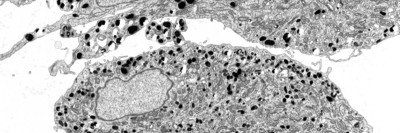

Pictured: Stem cell-derived nerve cells exposed to progerin

When stem-cell-derived nerve cells exposed to progerin (shown in green) begin to degenerate, their long, branch-like processes progressively shorten, then disappear. The top right cell is still healthy; the cell below it has begun to degenerate. The left-hand cell has lost its processes and is dying.